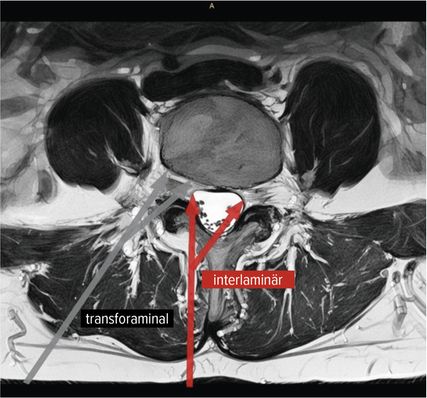

Der interlaminäre Zugang

Der interlaminäre endoskopische Zugang bietet Vorteile in den Segmenten L4/5 und L5/S1 aufgrund der Weite des Interlaminärfensters. Dem Chirurgen kommen dabei die Erfahrungen des offenen interlaminären Zugangs zugute, da die Ausrichtung des Sichtfeldes und anatomische Orientierung ident sind. Während der transforaminäre Zugang vorwiegend bei Diskektomien zum Einsatz kommt, hat die Entwicklung des IL-Zugangs das Indikationsspektrum erweitert. Zentrale Spinalkanalstenosen, Rezessusstenosen, aber auch die kontralaterale Foraminotomie sind mögliche Einsatzgebiete.11–13Abbildung 2 illustriert die interlaminäre (roter Pfeil) und transforaminäre (grauer Pfeil) endoskopische lumbale Zugangstrajektorien (MRI-t2-gewichtet). Abbildung 3 zeigt das Kambin-Dreieck. Dieses weist die Form eines rechtwinkligen Dreiecks auf und wird durch die austretende Nervenwurzel (Hypotenuse), den Duralsack, den Processus articularis superior des Facettengelenkes und die Grundplatte (Basis) begrenzt. Es stellt eine sichere Landungszone für das Endoskop im Neuroforamen dar.